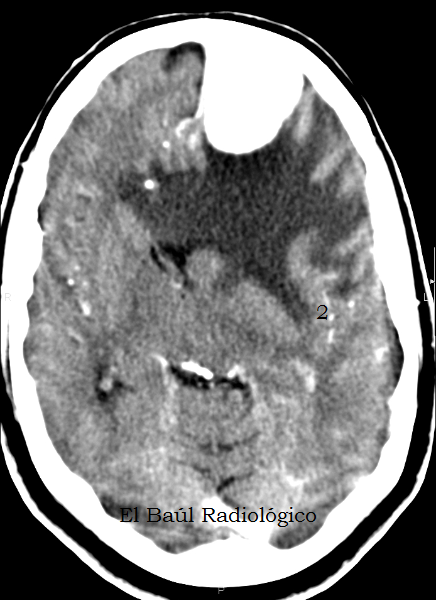

IMÁGENES SIN CONTRASTE ENDOVENOSO

Todas las exploraciones de Tomografía Computarizada craneoencefálica deben realizarse primero sin contraste endovenoso. Y, dependiendo de los hallazgos encontrados, se repite el examen despues de administrar una dosis de contraste. Si no se hace así podemos llevarnos alguna sorpresa.

FIGURA 2) Corte más cefálico, con edema digitiforme. Suele asociarse a tumores malignos. ¿Podemos detectar con certeza la causa que lo ha producido? No.

(A more cephalad CT image, with digitiform edema. It is usually associated with malignant tumors. Can we identify, with certainty, the cause that has produced it? No)